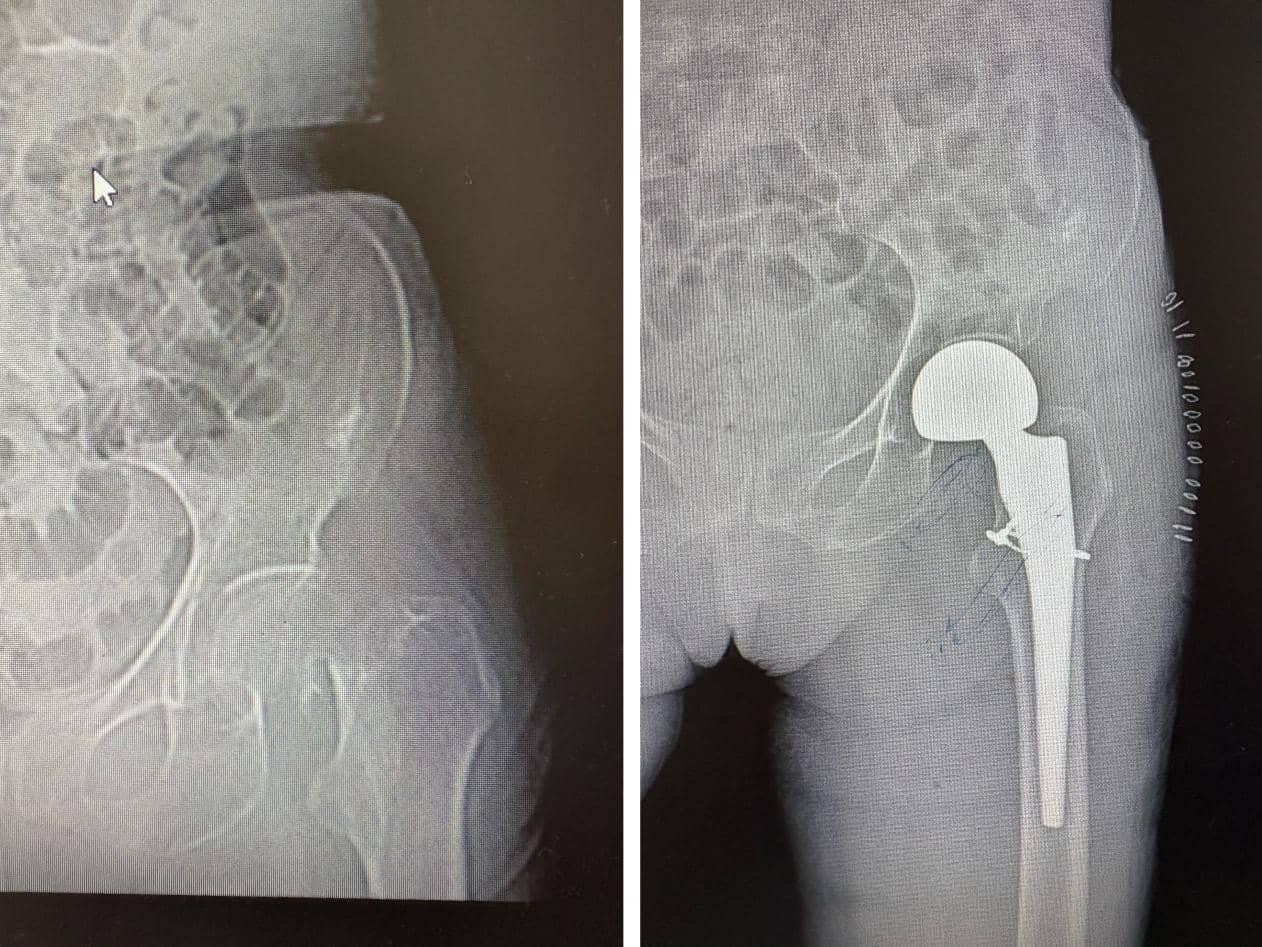

微创置换,78岁髋折老人3天下床

“原以为摔断了胯得躺上大半年,没想到术后3天就能下地!”78岁的李奶奶因在家中滑倒导致左侧股骨颈骨折,入院时不仅疼痛难忍,还伴有高血压、糖尿病等基础病,传统手术风险较高。创伤骨科团队综合评估后,决定采用微创人工股骨头置换手术,精准完成假体植入,术中出血量不足100毫升。术后第二天,李奶奶就能在床上自主翻身;第三天,在医护人员指导下能借助助行器稳步行走,彻底打消了“长期卧床”的顾虑。